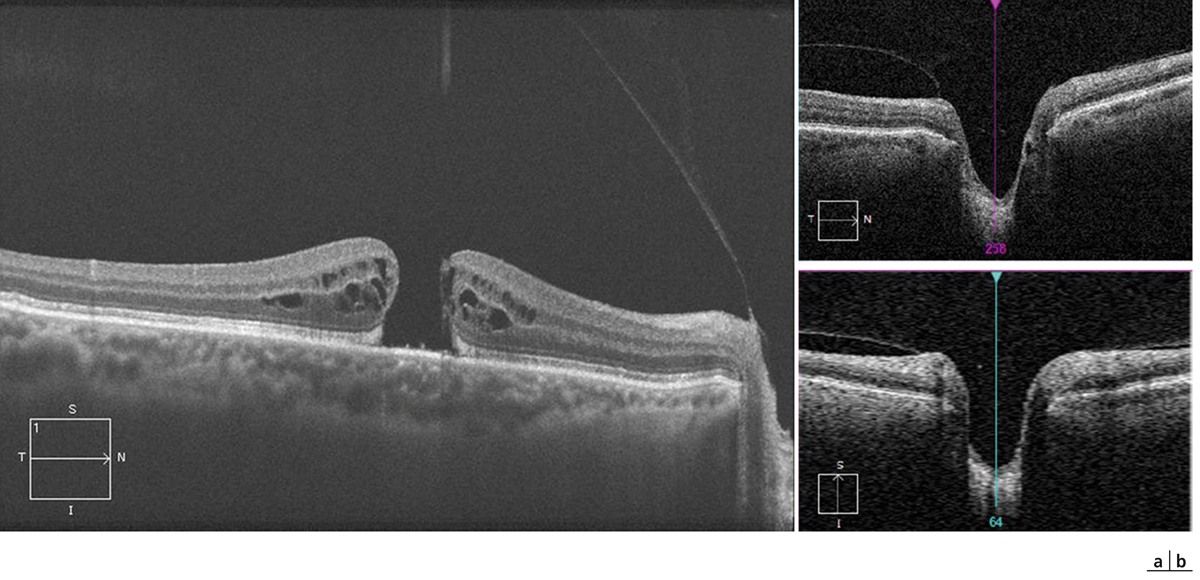

Fig. 13-11 Aspects biomicroscopiques de trous maculaires de pleine épaisseur.

a. Lésion arrondie à bords nets et épaissis. b, c. Des lésions punctiformes blanc jaunâtre en nombre variable peuvent être présentes au centre du trou maculaire et correspondent à des proliférations focales de l’épithélium pigmentaire.

Fig. 13-12 Mesure de la taille du trou maculaire en OCT.

La coupe doit passer par le centre du trou maculaire et la mesure doit être effectuée parallèlement à la ligne de l’épithélium pigmentaire, au niveau le plus étroit du trou correspondant à l’intervalle entre les deux extrémités des photorécepteurs soulevés (croix blanches).

Fig. 13-13 Évaluation du décollement de la hyaloïde postérieure en OCT sur une coupe de grande longueur (9 mm) passant à la fois par la région fovéolaire et par le nerf optique (a) ou à l’aide de la réalisation d’un cube OCT centré sur le nerf optique (b).

a. La hyaloïde est détachée de l’aire maculaire mais reste attachée à la papille (trou maculaire de stade III). b. Sur le cube centré sur le nerf optique, l’attache papillaire est également bien visible, ici sur les coupes horizontale (en haut) et verticale (en bas).